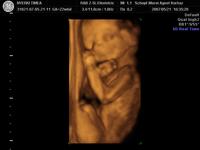

Megjártuk tegnap a 4d-t. Igazatok volt.Szuper volt látni a kis Törrpét. Az ujjacskáit, lábiját, kis pofit. Párom szerint már most is látni, hogy a nózit tőle örökölte. :D

Mi a Schöpf-Méreiben voltunk. (www.mamakalauz.hu)

18 percet vettek fel dvd-re. Kinyomtattak 4 szines képet és 1 darab 2 d-st, és az internetes honlapjukra még feltettek 20 képet amit 30 napig le lehet tölteni.Ár 13000

Ha mégegyszer akarunk menni akkor 5000 forint kedvezményt kapunk.

A hölgy nagyon kedves volt, mindent elmondott és megmutogatott. A rendelő pedig pontosan az amit az interneten feltettek képet.

Megpróbálok pár képet feltenni. Kép Tornászbajnok Kép Szundi Kép Szundi méhlepényes takaróval